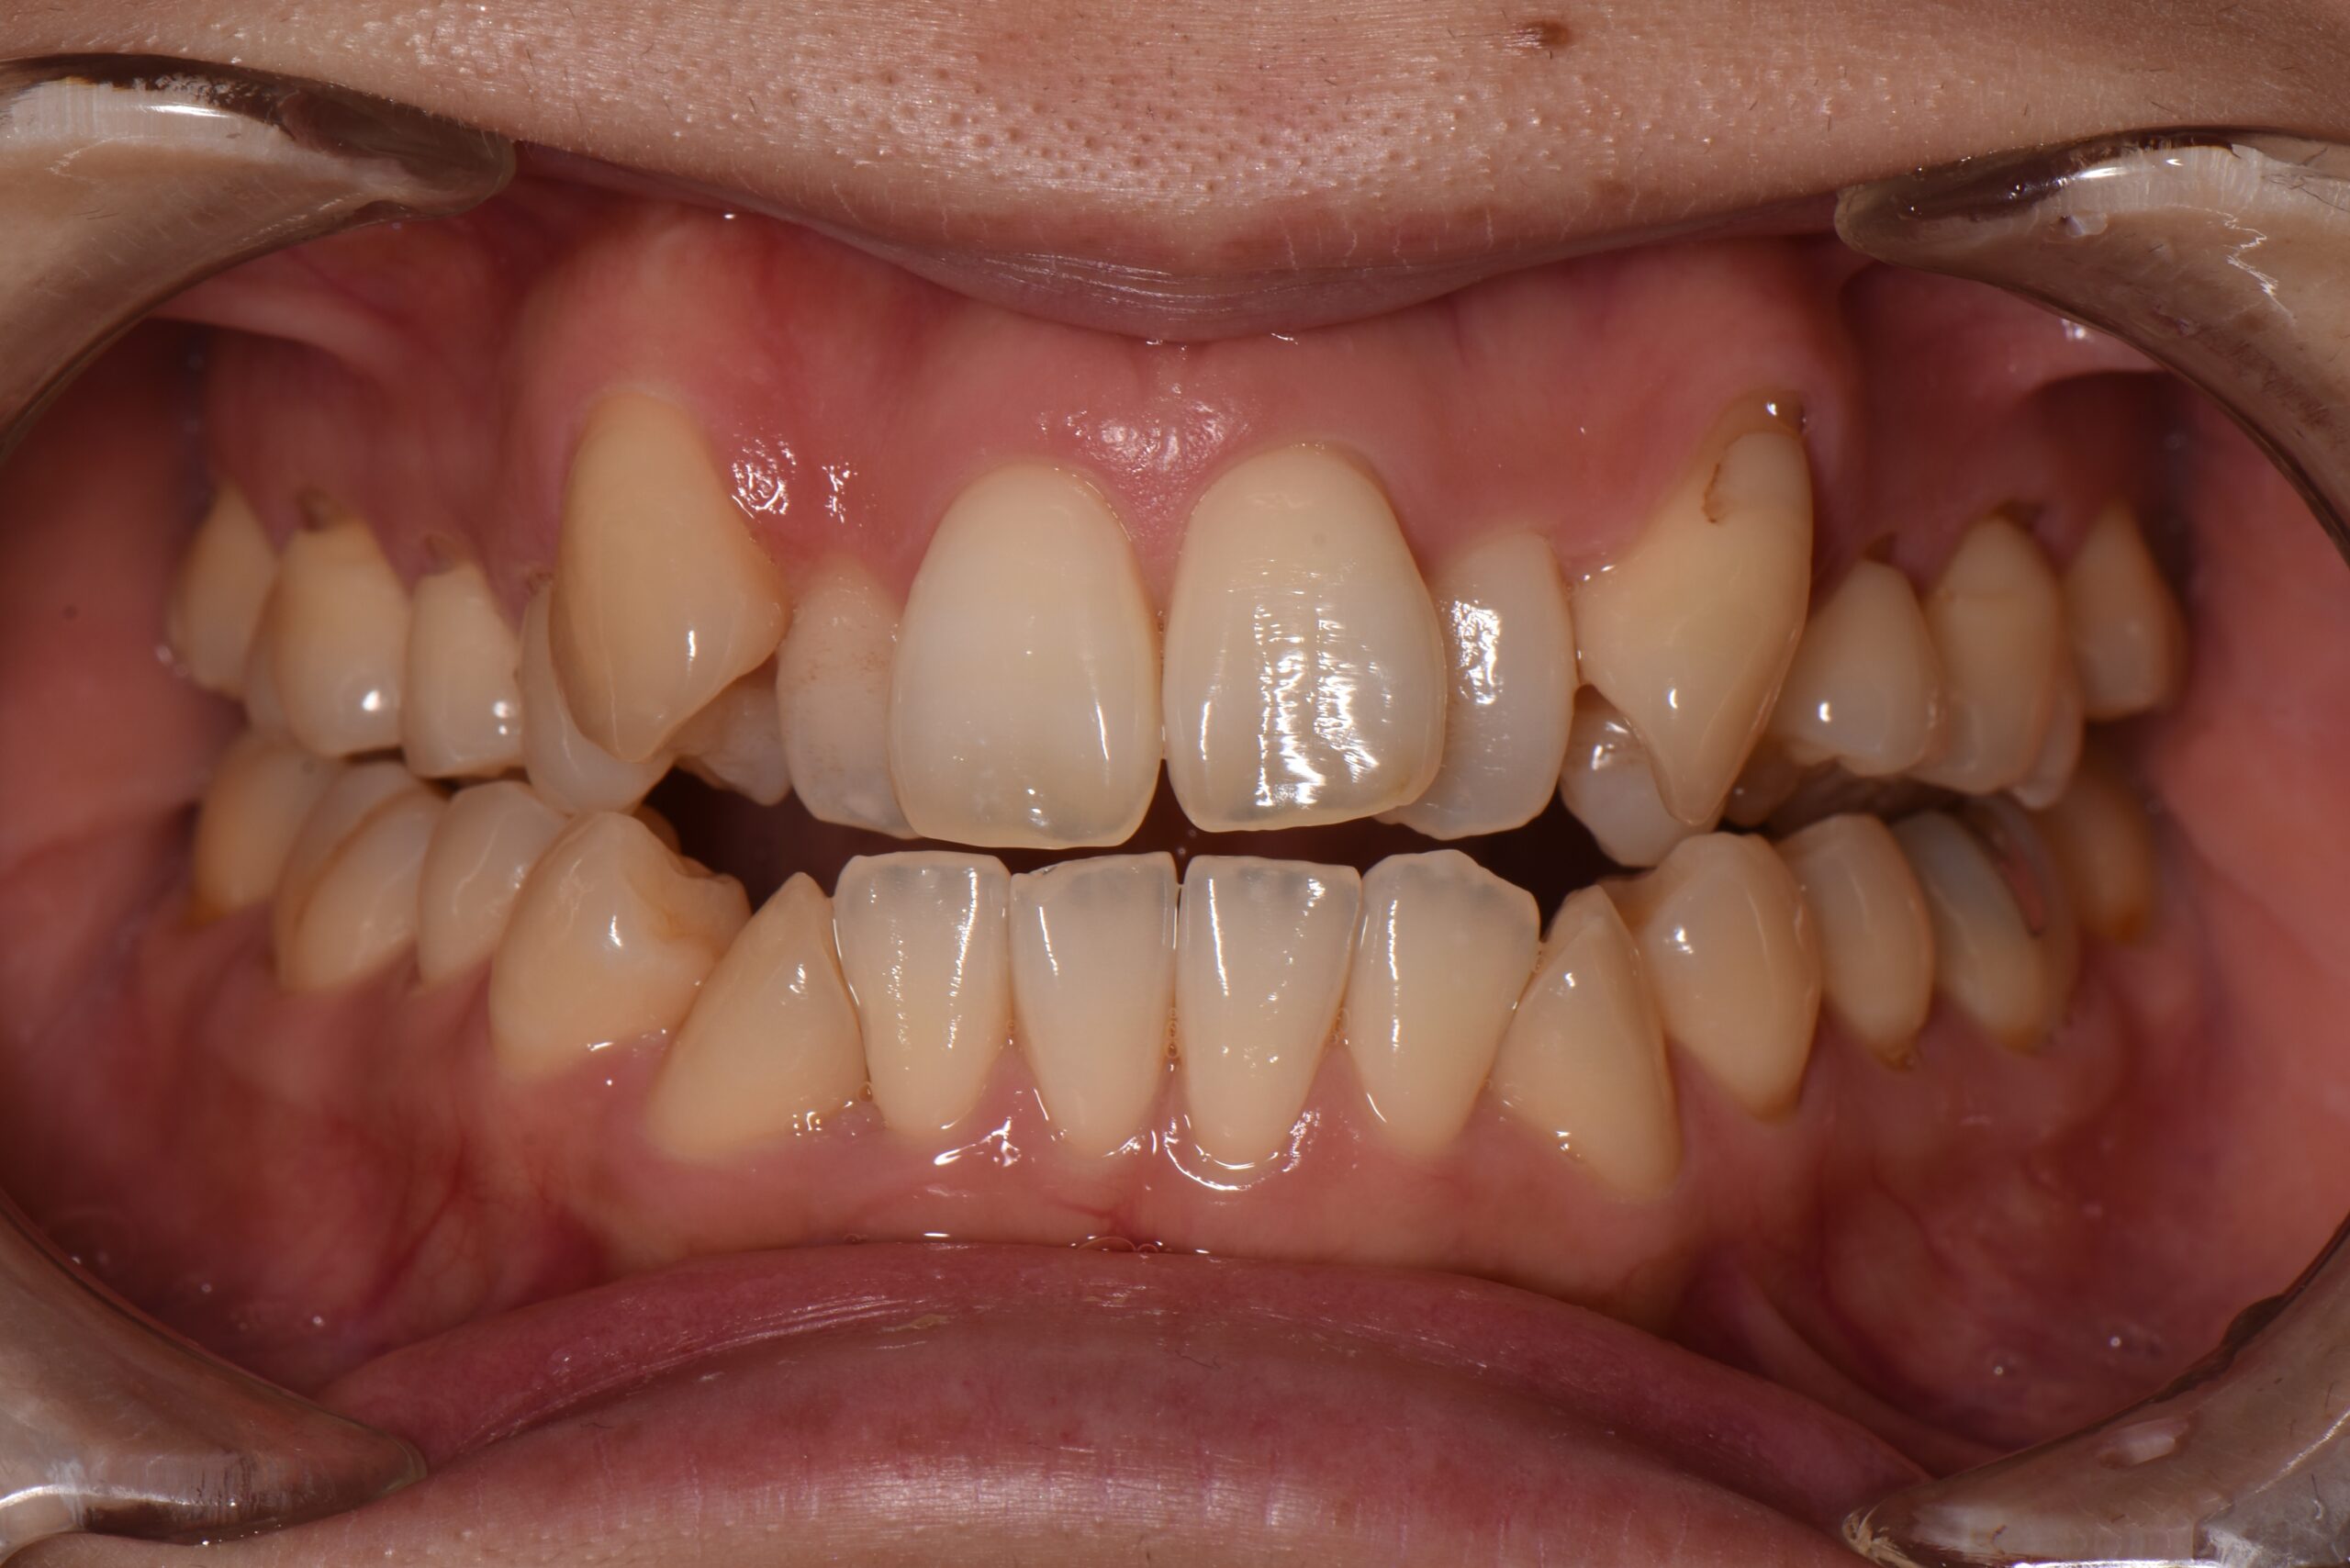

犬歯が外側に飛び出して、他の歯に重なっている状態です。八重歯は噛み合わせに問題が生じたり、歯磨きがしにくいことでむし歯や歯周病の原因となることがあります。